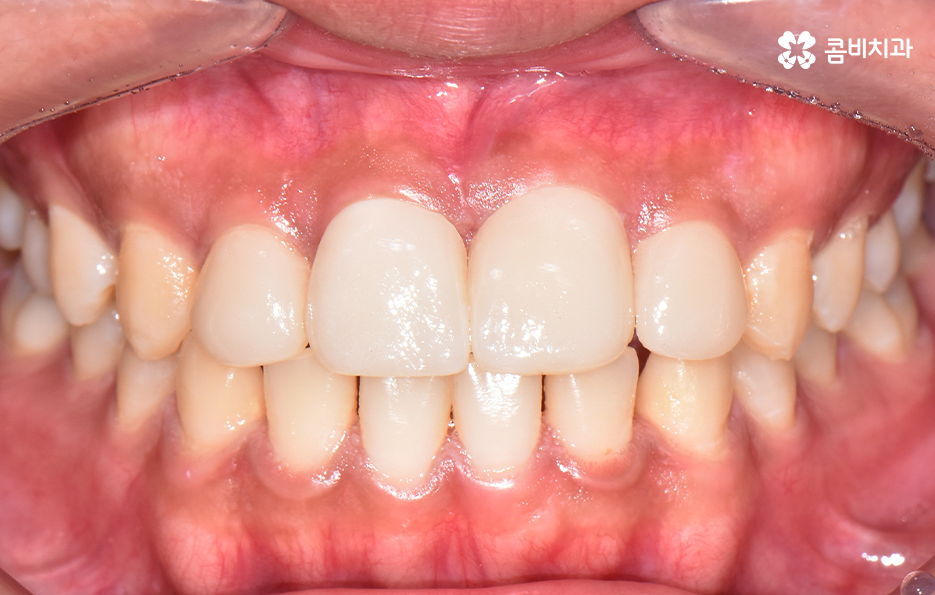

치아교정 기간은 각 환자분들에 따라 천차만별이기 때문에 정확하게는 각 환자분들의 상태를 직접 확인해봐야 하며 누구나 앞니만 부분적으로 교정이 가능한 것은 아니기 때문에 정밀검진이 우선적으로 필요하며 위 환자분의 경우에는 과잉치를 발치하고 교정기 장착 후에 약 6개월 정도가 지나서 교정기를 떼어낼 수 있었어요

앞서 말씀드린 것처럼 치열 전체로 보자면 전체교정을 통해 보다 심미적이고 치아의 건강, 기능적인 부분을 좀더 개선할수도 있었겠지만 오랫동안 앞니로 인해 콤플렉스를 갖고 지내다보면 앞니만이라도 빠르게 결과를 얻고 싶어 하는 환자분의 니즈도 있게 되고 전체교정을 하면 그에 따른 교정 기간과 비용적인 부분도 크게 증가하기 때문에 앞니 위주로 교정을 한 사례라고 보면 좋을 거예요

오늘 보여드린 케이스는 과잉치를 개선하면서 앞니의 치열도 함께 개선한 사례라면 요즘은 앞니가 약간만 벌어져도 교정을 고민하시는 분들도 많기 때문에 유독 앞니 위주로 벌어져서 고민이거나 나이가 들면서 잇몸이 약해지고 치열의 일부가 틀어진 경우에도 부분교정과 같은 치료 방법이 활용될 수 있는데요